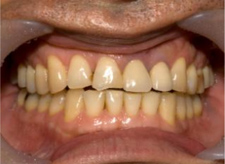

症例

初診

【主訴】

左上真ん中の歯茎が腫れた